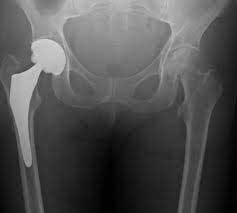

“It has been long debated that patients with orthopaedic implants, primarily hip and knee replacements, are prone to implant infections from routine dental procedures,” added Dr. Jevsevar who also is an orthopaedic surgeon in St. George, Utah. “What we found in this analysis is that there is no conclusive evidence that demonstrates a need to routinely administer antibiotics to patients with an orthopaedic implant, who undergo dental procedures.

· In 2010, there were more than 302,000 hip replacement and 658,000 knee replacement procedures performed in the United States.1

· Infections can occur when foreign organisms enter the wound during or at any point following joint replacement, and can lead to additional surgery and prolonged antibiotic treatment.2

· For studies of hip and knee included in this guideline, the mean rate of infection was 2 percent.3